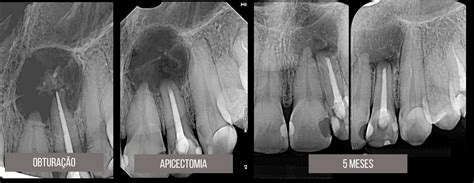

Antes de nada, el dentista debe evaluar la situación de la raíz (y los tejidos adyacentes). Para ello, realizará una radiografía o escáner 3D.

Con toda la zona ya saneada y limpia, hay que sellar la punta de la raíz. Normalmente en un par de semanas la zona externa estará cicatrizada.

En las primeras 24-48 horas es habitual que la zona tratada presente inflamación y dolor. El proceso de cicatrización de los tejidos blandos puede tardar entre 1 y 2 semanas. La cicatrización completa del hueso y la zona apical puede tardar varios meses.